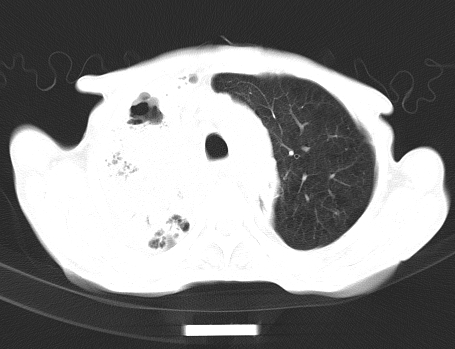

以下是引用gaoshengjiang在2008-5-30 19:53:00的发言:[br]右上叶可见大片实变影,其内可见充气支气管影及囊状影,右上叶尖端支气管走形区可见结节样影,左侧胸腔内可见胸腔胃影。纵隔淋巴结肿大。[br]考虑:1.右上肺阻塞性肺炎伴肺脓肿形成。支持转移所致。[br] 2.左侧胸腔胃。